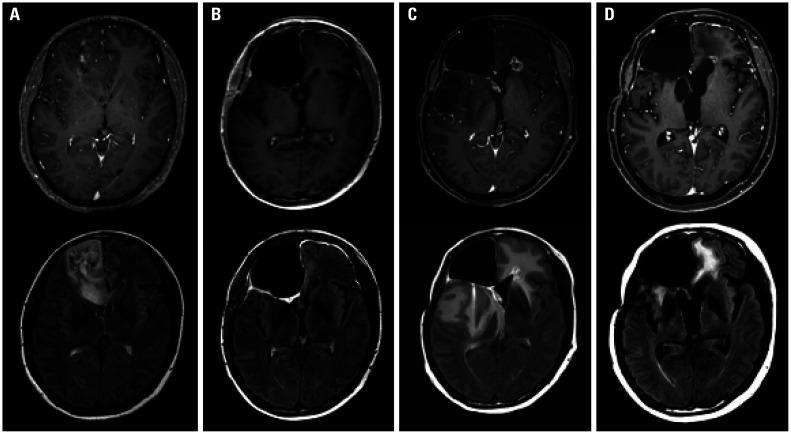

A total of 67 patients treated between 2009 and 2019 were analyzed. SRN was defined according to the following three criteria: 1) radiographic findings, 2) symptoms attributable to the lesion, and 3) treatment resulting in symptom improvement. Various contours, including the fornix, were delineated. Univariate and multivariate analyses of the relationship between RT dose and SRN, as well as receiver operating characteristic curve analysis for cut-off values, were performed.

The most common location was the frontal lobe (n=40, 60%). Gross total resection was performed in 38 patients (57%), and 42 patients (63%) received procarbazine, lomustine, and vincristine chemotherapy. With a median follow-up of 42 months, the median overall and progression-free survival was 74 months. Sixteen patients (24%) developed SRN. In multivariate analysis, age and maximum dose to the fornix were associated with the development of SRN. The cut-off values for the maximum dose to the fornix and age were 59 Gy (equivalent dose delivered in 2 Gy fractions) and 46 years, respectively. The rate of SRN was higher in patients whose maximum dose to the fornix was >59 Gy (13% vs. 43%, =0.005).

分析了 2009 年至 2019 年间治疗的 67 例患者。根据以下三个标准定义 SRN:1)影像学发现,2)归因于病变的症状,3)治疗导致症状改善。对包括穹窿在内的各种轮廓进行了描绘。进行了 RT 剂量与 SRN 之间的单变量和多变量分析,以及截断值的受试者工作特征曲线分析。

最常见的部位是额叶(n=40,60%)。38 例患者(57%)行大体全切除,42 例患者(63%)接受洛莫司汀、丙卡巴肼和长春新碱化疗。中位随访 42 个月,中位总生存期和无进展生存期为 74 个月。16 例患者(24%)发生 SRN。多变量分析显示,年龄和穹窿最大剂量与 SRN 的发生有关。穹窿最大剂量和年龄的截断值分别为 59 Gy(2 Gy 剂量等效)和 46 岁。穹窿最大剂量>59 Gy 的患者 SRN 发生率较高(13%比 43%,=0.005)。